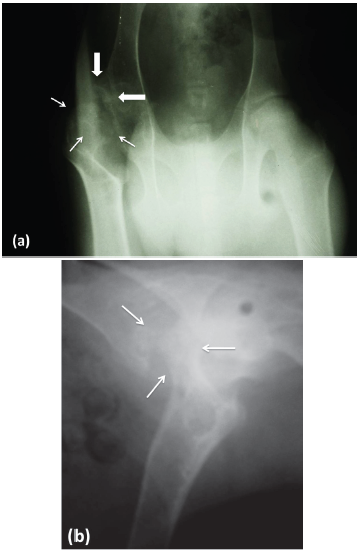

Diagnostic help. In order to complement the clinical diagnosis, pelvic radiographs were performed in two incidences (middle lateral and ventro dorsal). The right coxal articulation showed: increased joint space, irregular shape of the femoral head and neck and periarticular osteophytosis (Figure 2).

Figure 2 Hip x-ray in ventrodorsal incidence (a) and lateral mid incidence (b) of a 7-month-old male alpine goat. Right coxal articulation: irregularity and porous aspect of the femoral head with areas of decreased density in the epiphysis, compatible with focal bony lysis (thin arrows). The cranial - lateral area of the acetabulum has osteophytes (thick arrows). Flattening and irregularity of the articular surface of the head of the femur that causes subluxation of the joint.

In this case, the simple radiography was the tool used to approximate the diagnosis of AVNFH, which showed irregular bone density and degenerative changes typical of osteonecrosis of the head and neck of the femur. Radiologically, signs of osteonecrosis were observed, with a decrease in the radio-density of the femoral head and abnormal contours of the same 1. These findings agree with the findings available in experimental studies in goats and sheep 12.